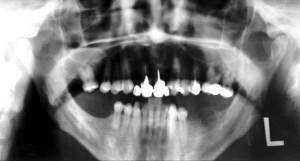

| Суставная дисфункция | Травмы, воспаления, нарушения прикуса | Жевательную мышцу часто сводит внизу, происходит непроизвольное плотное смыкание челюстей (рекомендуем прочитать: ) | Рентгенография, КТ, УЗИ, ортопантомография |